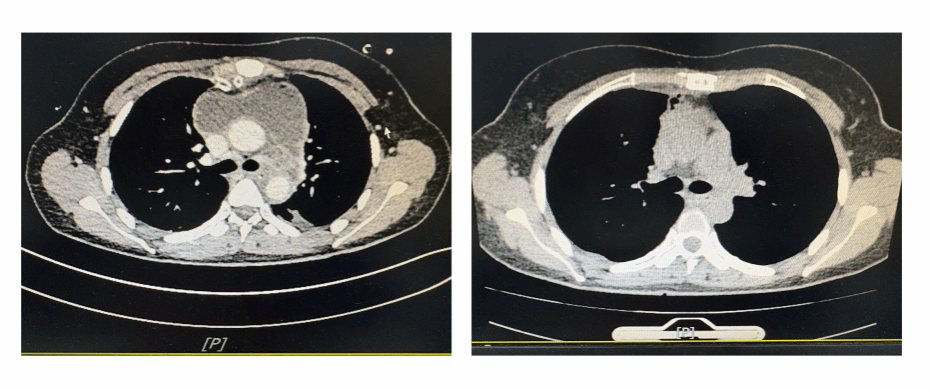

患者及家属遂就诊我院呼吸与危重症医学科,接诊时,郭女士情况危急,颌面部、颈部肿胀明显,张口困难,呼吸急促,考虑拔牙引起的颈部感染。入院后立即完善颈、胸部 CT 检查,结果凶险程度远超预期,不但在她的双侧颌下、颈部间隙形成脓肿,而且脓肿已沿筋膜间隙蔓延至纵隔,在前纵隔形成巨大脓腔,侵及大血管及食管,双侧肺也继发感染,随时可能有生命危险。

图1术后/术前胸部CT对比